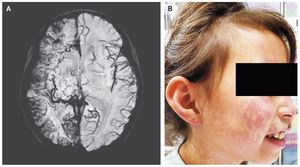

A 6-year-old girl was brought to the emergency department after the sudden onset of weakness in the left arm and leg. She also reported a 2-day history of pain in her right eye. No seizure activity had been witnessed. She had a nonpalpable red lesion on the right side of her face, and the intraocular pressure was elevated in both eyes. Magnetic resonance imaging (MRI) of the head revealed right cerebral atrophy with leptomeningeal enhancement along the right cerebral convexity. Susceptibility-weighted MRI (Panel A) revealed abnormal leptomeningeal capillary vessels along the right cerebral convexity. The MRI and clinical findings were consistent with the Sturge–Weber syndrome, a rare congenital vascular disorder characterized by a cutaneous capillary malformation, also called port-wine birthmark (Panel B shows the patient’s face 2 years after the initial presentation), and abnormal capillary venous vessels in the brain and eye that can lead to glaucoma, seizures, stroke, and intellectual disability. The weakness on the left side, which was thought to be postictal paresis, resolved within 24 hours. An antiepileptic medication was prescribed, as well as timolol and dorzolamide for glaucoma and daily low-dose aspirin treatment to reduce the risk of thrombotic events. Over the next 2 years, she had two presentations with seizures, which led to adjustment of the antiepileptic regimen. Shivang Desai, M.D. Charles Glasier, M.D. University of Arkansas for Medical Sciences, Little Rock, AR source: nejm.org